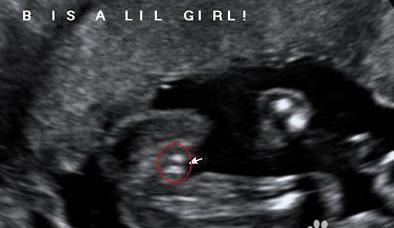

生男生女早知道, b超看胎儿性别图解

虽然说作为不是医学专业的我们,要看这种复杂的b超图,一开始显然是极度的茫然,但是,其实掌握几个点,也完全可以自己去揣测b超图中的信息,下面我来说下b超图怎么看胎儿性别,b超看胎儿性别图解。

首先,是我们看B超图中是否有三条线,很显然的,如果有三条线存在,那么说明胎儿是女姓,没有则是男娃。

其次,看B超图是否有明显凸出的地方,如果有,而且类似一团菌状,那也很显然,这个胎儿是男性,没有则是女娃。